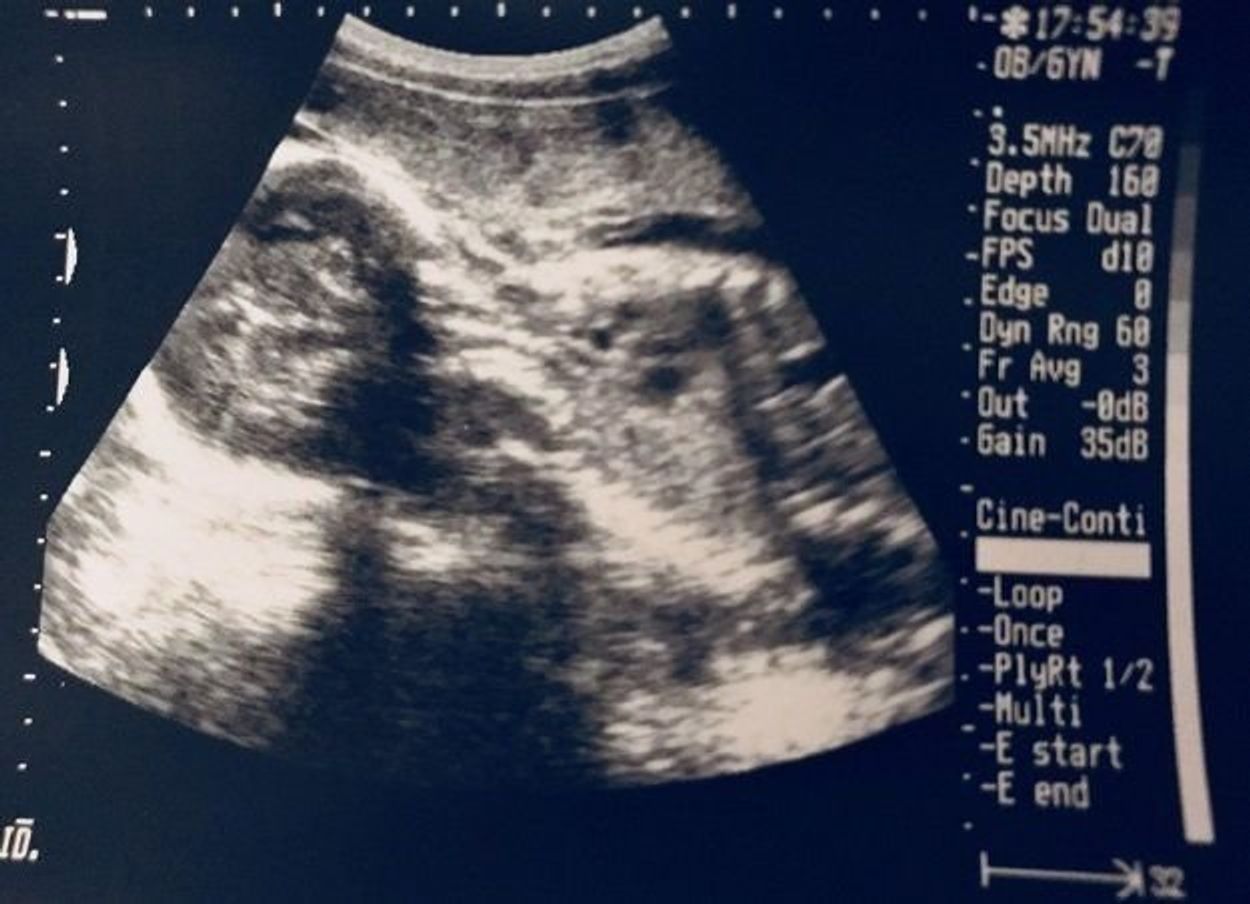

当時の実際のエコー写真をご紹介したいと思います。 ※エコー写真が苦手な方はここで引き返してください。 ⇩その時の写真がこちら⇩ 女の子の特徴である三本線ははっきり見えずに足と足の間に、突起物のようなものが見えるのが分かりますか? 妊娠 女の子 特徴 卵子と精子が出会って受精した瞬間に赤ちゃんの性別が決定しますが、実際にエコーなどで性別が判明するのはだいたい5ヶ月目以降です。

妊娠30週目の女の子のエコー写真 女の子を見分けるのは足の間の突起物が無いかコーヒー豆が見えるか! 女の子の性別判定はいつから可能? 女の子の性別判定はいつから可能なのでしょうか? 男の子も女の子も外性器がしっかりと形成され、 性別判定 腹部エコーでは正確な判断が出来ません。 腹部エコーって? 腹部エコーの特徴はエコーは幅が広く、 深部まで映ります。 12週目以降になると経腟エコーだと 胎児が大きすぎて映らなくなります。 私たちが普段よくとる カメラと同じ 感じですね。 男女の性別の特徴が よりはっきりと診断できるようになるのは、 妊娠24週目(妊娠7ヶ月目)に入ってから。 途中で性別判定がコロコロ変わるなんて嫌ですもんね。 男の子か女の子か気になる妊婦さん必見です! エコー検査での見え方の特徴もご紹介します。